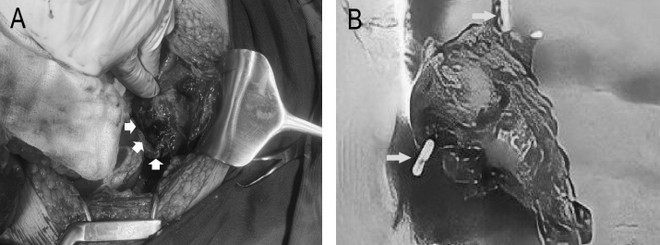

Một bệnh nhân bị thủng tử cung do đặt dụng cụ tránh thai 30 năm ảnh 1Hình ảnh chụp cắt lớp vi tính. Dụng cụ tử cung xuyên qua thành tử cung vào ruột (mũi tên trắng). (Ảnh: BVCC)

Qua siêu âm ổ bụng các bác sỹ thấy các quai ruột ứ đọng dịch, giảm nhu động, ít dịch tự do ổ bụng. Chụp cắt lớp vi tính thấy hình ảnh dịch khí tự do trong ổ bụng, tắc ruột cơ năng, dày thành ruột vị trí hố chậu phải và dị vật xuyên thủng đáy tử cung.

Theo bác sỹ Trường, đa số dụng cụ tránh thai sau khi thủng sẽ nằm ở khoang phúc mạc sau đó xâm lấn vào các cơ quan lân cận gây biến chứng thủng ruột. Do đặc điểm lỗ thủng ruột thường là nhỏ nên tình trạng viêm phúc mạc có thể ở mức độ nhẹ, khu trú, thậm chí không có triệu chứng. Ngược lại nếu dịch tiêu hóa lan rộng gây viêm phúc mạc toàn thể với lâm sàng cấp tính, đau bụng, nhiễm trùng khiến bệnh nhân phải nhập viện. Chụp cắt lớp vi tính là lựa chọn để chẩn đoán trong bệnh cảnh viêm phúc mạc. Đặc điểm dụng cụ tránh thai lạc chỗ với dấu hiệu dị vật ổ bụng nằm ở tiểu khung, thâm nhiễm viêm, dày thành quai ruột, đôi khi có dịch khí tự do ổ bụng.